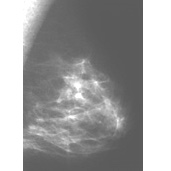

The image on the left shows the mammogram of a normal breast, while the image on the right shows a mammogram with an abnormality detected (denoted by the red arrows). Click on the images to visit their source, the Breast Center of St. Louis University.